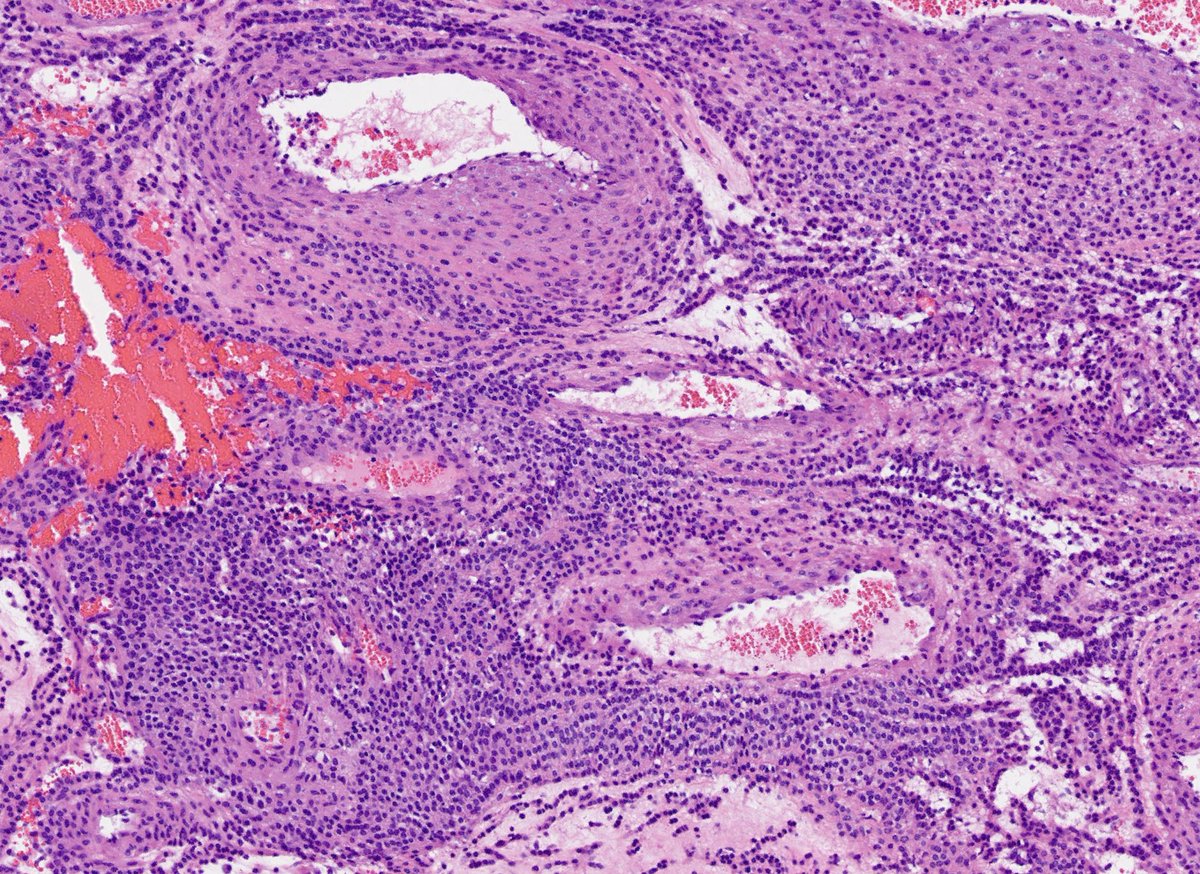

Explants from woman in her mid 40s. Clinical history on req: pulmonary hypertension. IHC is CD1a. Unifying diagnosis?

Thanks to all who engaged! Although uncommon, chronic LCH can lead to severe secondary pulmonary HTN which is what we see here. A spectrum of arterial lesions, including plexiform, dilatation, and medial hypertrophy. Wishing the patient a new lease on life with new lungs!